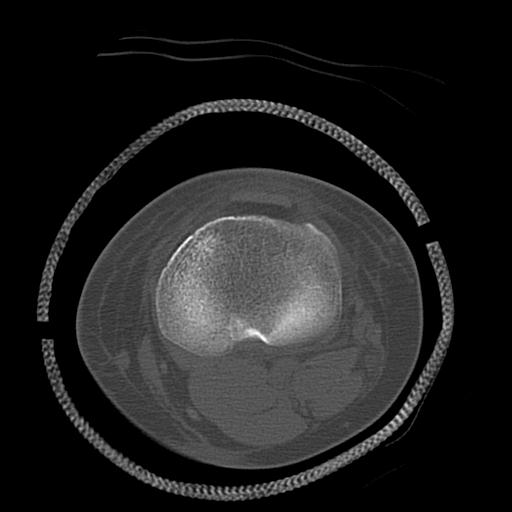

49554 3/13 膝 4R 3/16 4R 1/18 2R 78歳男性 膝蓋骨骨折

100612 11/25 1/20 右膝 2R 84歳女性 右TKA

91983 11/16 左膝 2R 11/18 2R 55歳男性 脛骨骨切り術